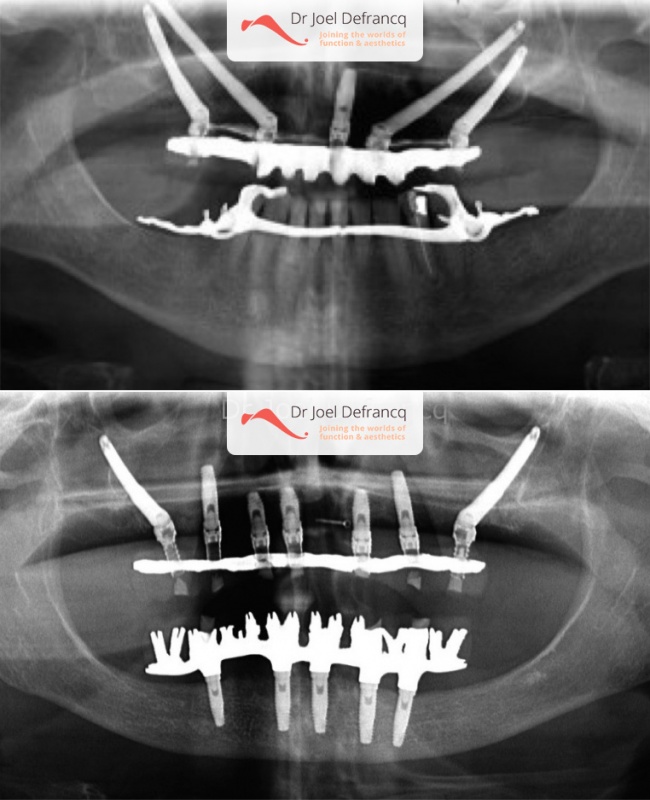

In de jaren ’90 startte P.I. Bränemark uit Zweden met een techniek waarbij het bot dat de jukbeenderen vormt, gebruikt wordt als ankerpunt voor het plaatsen van dentale zygoma-implantaten. In het jaar 2003-2004 werden hiervan resultaten en data gepubliceerd die gelijkaardige succesratio’s vertoonden als bij conventionele implantaten.De techniek van de plaatsing van zygoma-implantaten werd gedurende de laatste twintig jaar ontwikkeld en is als zodanig niet echt een punt van discussie. Er wordt niet gerekend op verankeringsmogelijkheden van het alveolaire kaakbot, zoals bij de conventionele implantaten. De zygoma implantaten groeien enkel vast ter hoogte van de jukbeenderen. Deze implantaten zijnl langer (tussen 3,5 en 5 cm) dan de reguliere implantaten (tussen 0,7 en 1,5 cm).

Heel vaak kan één zygoma-implant aan elke kant gecombineerd worden met reguliere implantaten in het gebied van de voortanden. In meer extreme gevallen worden langs elke zijde 2 zygoma implantaten geplaatst en worden eveneens dadelijk belast.

Vooraleer de operatie plaatsvindt, nemen we een extended i-cat). Deze laat ons toe de beenderige structuren, in het bijzonder de jukbeenderen, driedimensionaal te bestuderen. Zygoma-implantaten worden onder algemene anesthesie geplaatst.

Optie 1: We plaatsen vier zygoma-implantaten in de totale en extreem atrofische bovenkaak (aangezien bot ontbreekt voor reguliere implantaten), gevolgd door een vaste suprastructuur (tanden) binnen de paar dagen. Een extra regulier implantaat ter hoogte van de voortanden is altijd aan te raden, omwille van een betere stabiliteit. Dit kan later veel klachten voorkomen.Optie 2: We plaatsen twee zygoma-implantaten in het gebied van de tweede voorkiezen en drie tot vier reguliere implantaten ter hoogte van de voortanden. Deze optie wordt ook gevolgd door een vaste suprastructuur (tanden) binnen de paar dagen.

Er is inderdaad meestal nog wat bot aanwezig in het voorste deel van de bovenkaak recht onder het neusgebied. Indien er enkele (twee tot vier) reguliere implantaten kunnen worden geplaatst in het gebied van de voortanden, zal dr. Defrancq dit altijd doen. De sinussen zijn in de meer achtergelegen delen van de bovenkaak gelegen, en ten gevolge van de sinusuitbreiding is er daar vaak niet genoeg bot aanwezig. Dr. Defrancq plaatst daar twee zygoma-implantaten. Een rechtstreekse belasting volgt altijd op de ingreep en de patiënt heeft binnen een week vaste porseleinen of chroom-kobalt tanden.